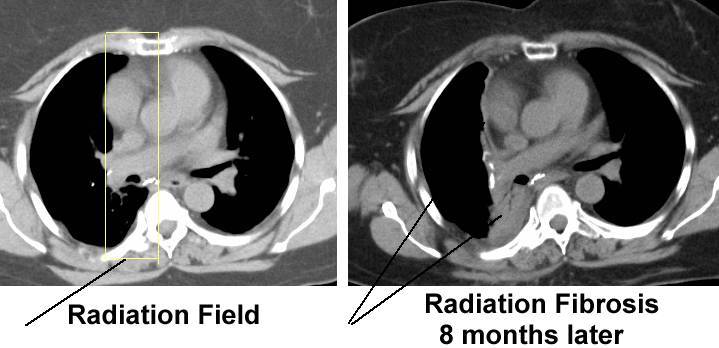

Long term toxicity effects of RT

Lung fibrosis, skin atrophy + infertility

Eventually causes fibrosis Borders are defined

Bronchitis/ pneumonitis (can occur 4 weeks - 6 months post treatment)